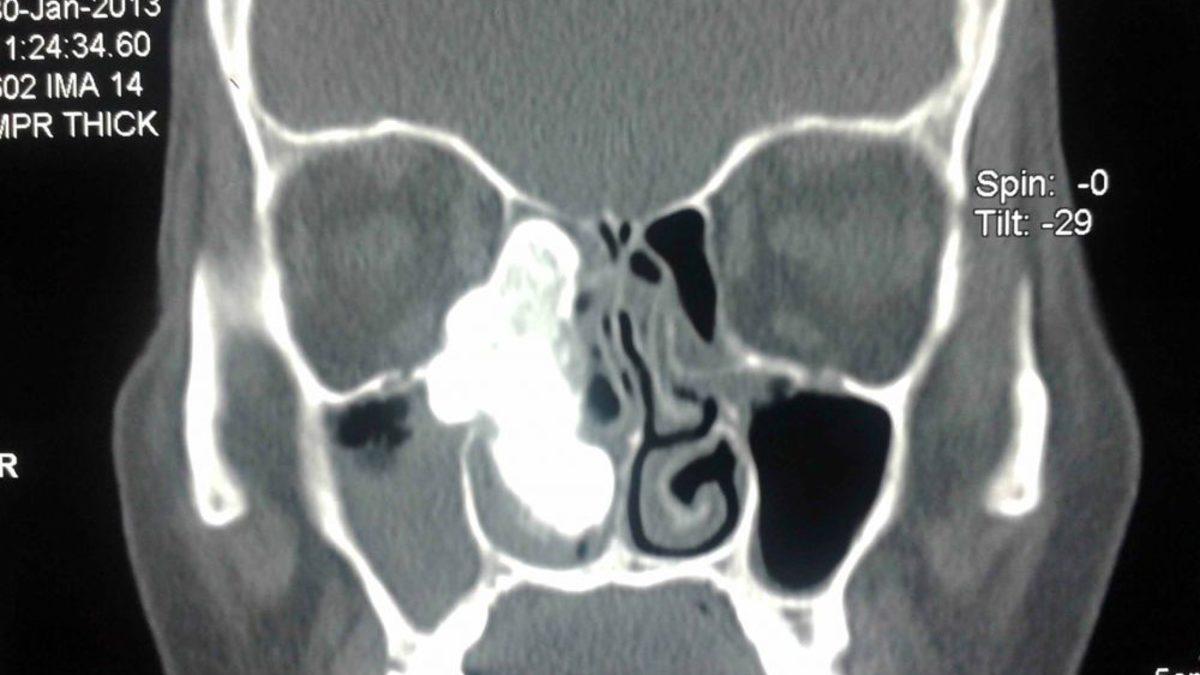

Erzincan'da burun tıkanıklığı ve baş ağrısı şikayetiyle Erzincan Mengücek Gazi Eğitim ve Araştırma Hastanesi Kulak Burun Boğaz Hastalıkları ve Baş Boyun Cerrahisi Kliniği’ne müracaat eden 60 yaşındaki Fatma Toygar'ın burun kanalı içerisinde ceviz büyüklüğünde tümör tespit edildi. Yapılan endeskopi muayenesi ve tomografi çekilmesinin ardından kadının yüzünün sağ bölümünde burun kanalı içerisinde yaklaşık 12 santimetre ebatında, ceviz büyüklüğünde kemik tümörü olduğu öğrenildi.